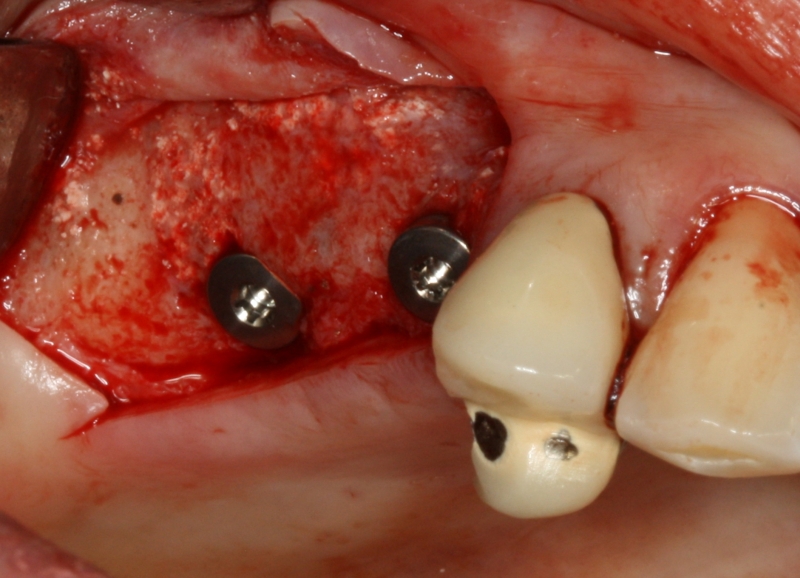

17/20 - implant placementGBR with maxresorb® & Jason® membrane - Prof. Dr. Dr. D. Rothamel